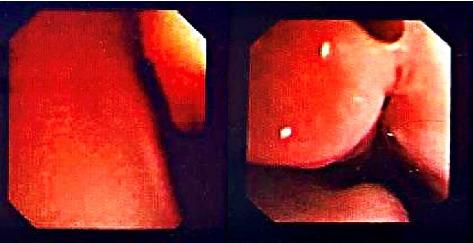

随着紫绀性呼吸暂停发作的持续时间延长,患者接受了气管插管,过程中未见肿块。据患儿母亲描述,紫绀性呼吸暂停发作通常发生在哭闹之后。心脏评估未发现异常。支气管镜检查发现后鼻孔变窄(图1)。考虑后鼻孔肿物或后鼻孔闭锁、气道软化。经过CT扫描发现鼻咽区域增强,不排除血管瘤、皮样囊肿、淋巴管瘤和畸胎瘤等肿块(见图2)。

图1 初次支气管镜检查期间观察到的后鼻孔狭窄